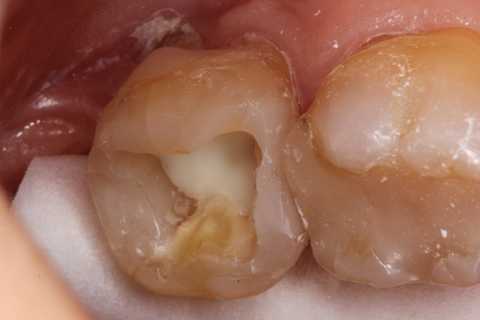

30代女性、左下7、Per、動揺度2.5

今日の症例は8年前に僕が親知らずが遠心に食い込んで虫歯になったものを神経を取らずにCR充填したものだが、とうとう接着剥がれが起こり神経が死んでしまった。神経は全く残っておらず。溶けてなくなっていた。

この症例は歯根内部をいじられていないので、根管治療は難しくない。CRで歯冠を再建するのが難しかった。

再建が終わった後で、内部の治療をしてCRで埋め戻している。